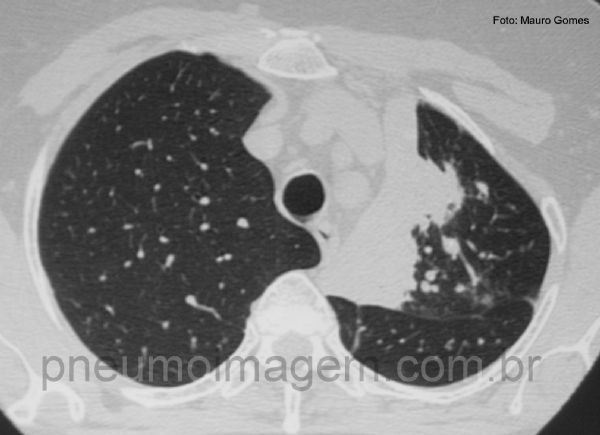

Neste corte tomográfico se observa a atelectasia parcial do lobo superior esquerdo. Há nódulos centrolobulares na periferia da lesão que podem corresponder a disseminação broncogênica da tuberculose.

In this CT slice is observed partial atelectasis of the left upper lobe. There are centrilobular nodules in the periphery of the lesion which may correspond to bronchogenic spread of tuberculosis.